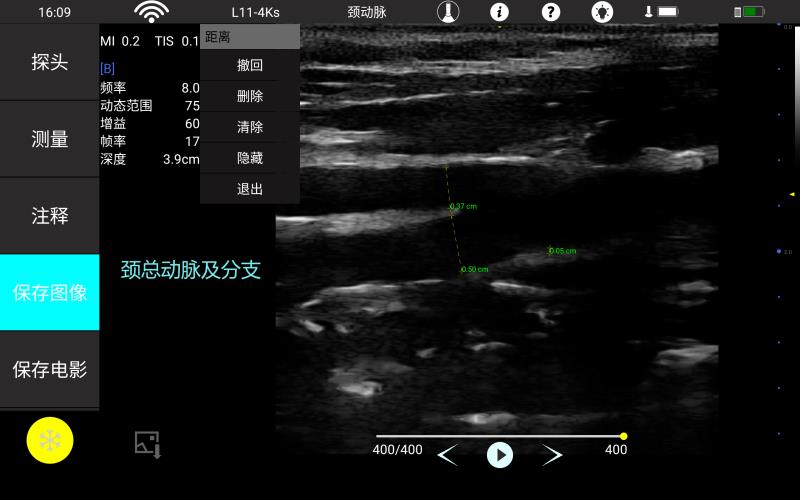

• 线阵

甲状腺

血管

神经

肌骨等